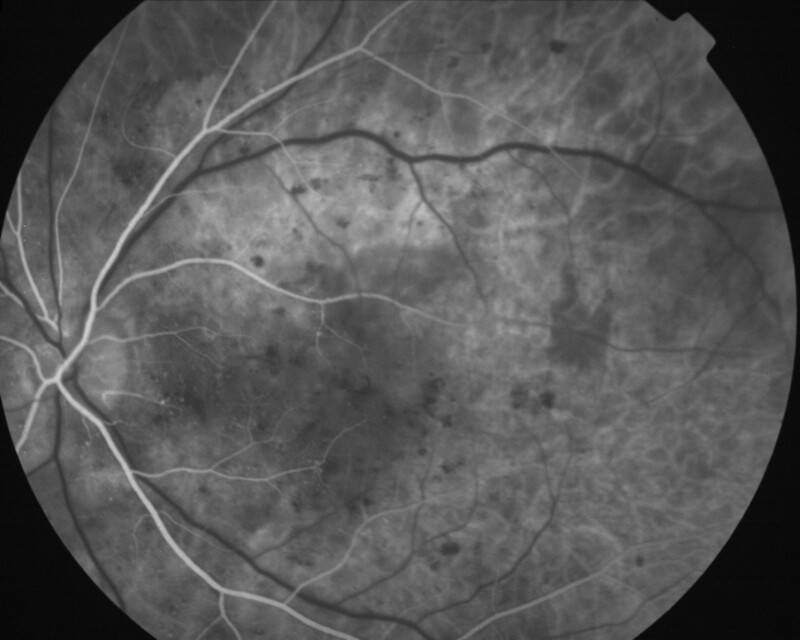

RETINOPATHIE DIABETIQUE NON PROLIFERANTE SEVERE